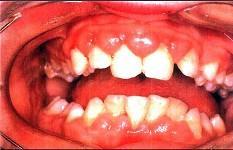

问题 患者,男性,19岁,主诉:前牙牙龈红肿肥大1年余。临床检查:上唇短,上前牙唇侧牙龈边缘及龈乳头增生肥大,覆盖牙冠的1/3,质地较韧。最可能的诊断是 ( )

选项 A.增生性龈炎 B.牙龈纤维瘤病 C.青春期龈炎 D.慢性龈缘炎 E.急性坏死性溃疡性龈炎

答案 A